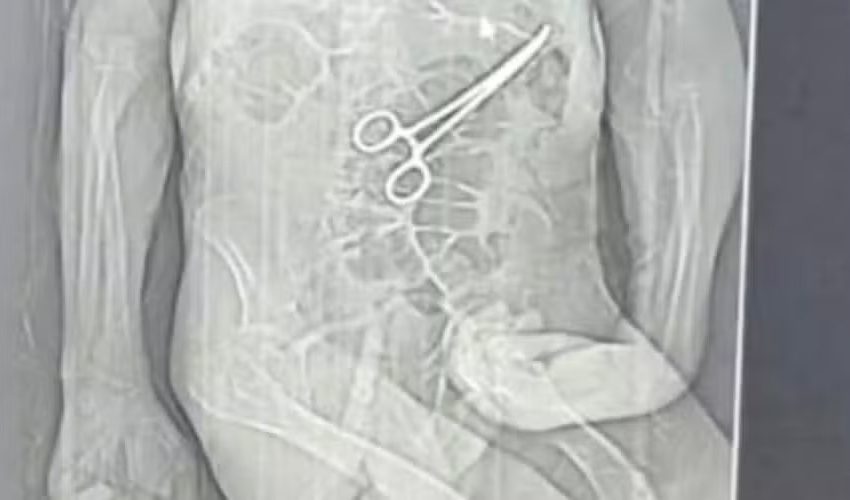

A Secretaria de Saúde de João Pinheiro, cidade no Noroeste de Minas Gerais, abriu uma sindicância para apurar a morte de um homem que teve uma pinça “esquecida” dentro do corpo, Read More